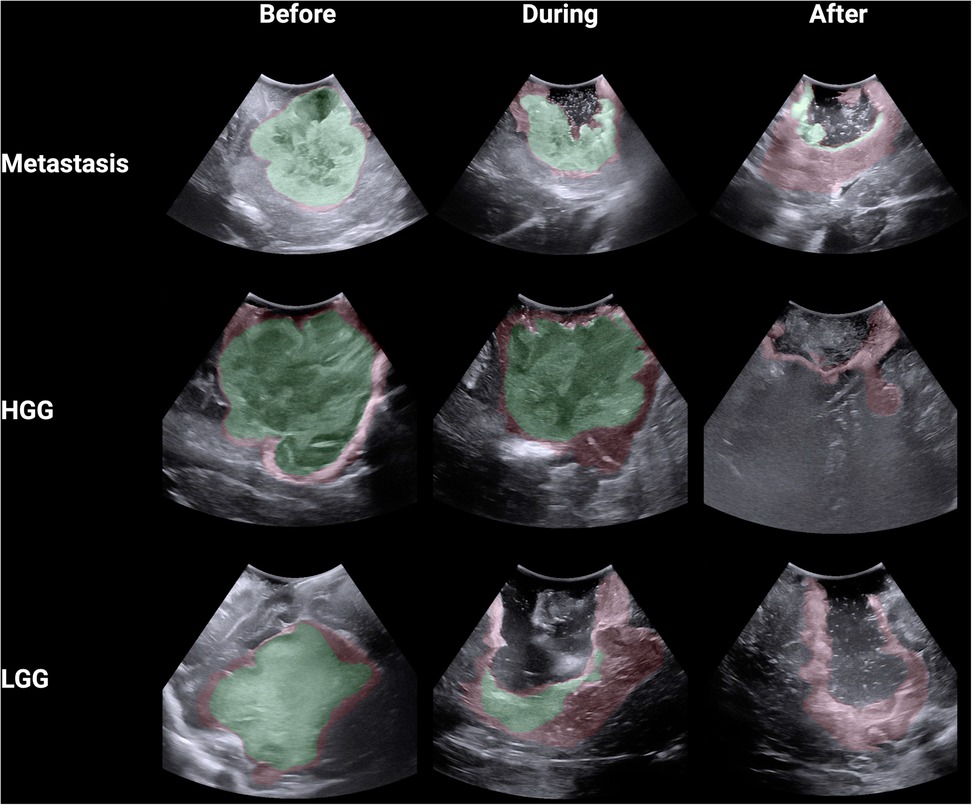

Using Python through the ChatGPT Data Analyst interface, segmentations were converted into binary masks and then analysed using the Digital Image Correlation Engine Similarity Coefficient (DSC) which measures the similarity between two images by comparing pixel patterns (12). DSC range from 0 to 1 with segmentations that are perfectly aligned getting a score of 1 and segmentations that are not aligned at all getting a score of 0. For each image, every observer was compared against the other, producing a DSC for each comparison. In this study, a total of 153 DSCs were calculated for each image across the 18 participants. Heat maps were created for each image by converting the binary masks into arrays and allocating each pixel an aggregate score based upon whether it was incorporated within the segmented tumour. Each pixel could have a score ranging from 0 (all participants deemed this pixel not to be tumour) to 18 (all participants deemed this pixel to be tumour). The following colour code was then allocated to the pixels based on their aggregate score: green (15–18), red (4–14) and white (0–4). This heatmap was made transparent and then overlaid onto the original iUS image. Comparisons between the stages of surgery and tumour type were performed with the Kruskal–Wallis test with Dunn's multiple comparisons test. Correlation between the average difficulty ratings and DSCs for the 9 iUS images was performed using Spearman's correlation. Comparisons between high and low experience surgeons across tumour type and operation stage was performed using two-way ANOVA with Tukey multiple comparisons test. Statistical analysis and graphical visualisation were conducted using R through the BioRender interface.

A total of 18 neurosurgeons participated in the study including 5 attendings, 7 fellows and 6 residents. From this group, a total of 1,377 DSCs were calculated across the 9 iUS images. Metastasis had the highest DSC (0.72 ± 0.32), followed by HGG (0.64 ± 0.33) and then LGG (0.58 ± 0.25; p < 0.00001) (Figure 2A). As the resection progressed, the degree of inter-observer agreement broke down. Before resection the DSC was 0.871 ± 0.105; during resection (0.74 ± 0.174) and at completion (0.32 ± 0.270; p < 0.00001) (Figure 2B). Observers reported increasing difficulty with iUS interpretation as the resection proceeded and there was statistically significant (p = 0.014) negative correlation (−0.775) between DSC and difficulty rating of the segmentation (Figure 2C). The trend of decreasing agreement as the resection progressed held across tumour types. It was most pronounced in HGG where there was a near complete breakdown of agreement in the resection cavity (0.26 ± 0.28) (Figure 3). Heats maps for the iUS demonstrated the spatial variation in observer agreement across the tumour types and stages of surgery (Figure 4). It shows decreasing agreement as the resection proceeds particularly within the margins of the resection cavity near the end of the resection. From the 18 participants, there were 5 observes who were highly experienced with iUS (>50 cases) and 6 observers with low experience (<10 cases). There was no significant difference in DSCs between the high and low experience observers across the tumour types and stages of surgery.

Figure 4. Spatial heat maps of observer agreement across 9 iUS images (green >80% agreement; red 20%–79% agreement).